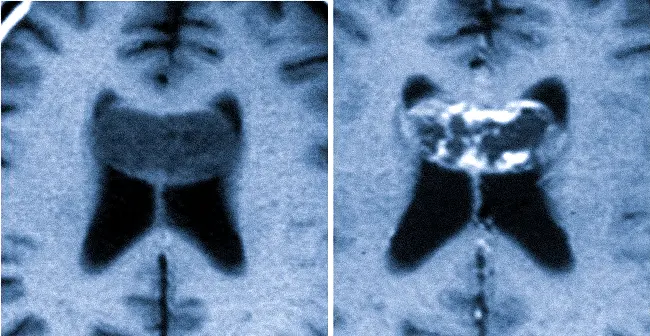

Астроцитома головного мозга на МРТ

Сравнение изображений без контраста и с контрастом: астроцитома мозолистого тела. Отображение опухолей на МРТ может различаться в зависимости от их гистопатологических свойств. Плеоморфная ксантоастроцитома имеет более четкие границы по сравнению с другими видами астроцитом, располагается ближе к поверхности и менее склонна к диффузному распространению.

Глиобластомы, в отличие от астроцитом первой и второй степени, показывают неоднородность структуры и значительное усиление после введения контрастного вещества из-за образования новых сосудов (неоваскуляризация), наличия некрозов и мелких кист. Точечные кровоизлияния могут обнаруживаться в структуре опухоли.

При прогрессировании онкологического процесса обнаруживаются скопления новых трансформированных клеток, находящиеся на расстоянии от основного очага, однако всегда в пределах центральной нервной системы. Уровень перифокального отека может варьироваться. На МРТ визуализируется избыточное накопление гадолиния.

Магнитно-резонансная томография также применяется для определения эффективности лечения. На основании изображений можно определить наличие частичного или полного ответа на терапию, стабильное состояние онкологического процесса или его прогрессирование. У пациентов, перенесших резекцию, точное сравнение снимков до и после операции может помочь различить остаточную опухоль и начальную рубцовую ткань на краях резекции. Из-за высокой вероятности злокачественной трансформации диагностику — МРТ головного мозга — всегда проводят с использованием контрастного вещества.

Астроцитомы мозга — это опухоли, которые формируются из астроцитов, поддерживающих клеток нейронов. Они могут быть как доброкачественными, так и злокачественными. Интерпретация МРТ-снимков при астроцитоме требует высококвалифицированного подхода, поскольку опухоли могут иметь различные характеристики и паттерны роста. Зачастую они проявляются как гиперинтенсивные образования на Т2-изображениях и гипоинтенсивные на Т1-форматах, но точная оценка зависит от контрастирования и других факторов.